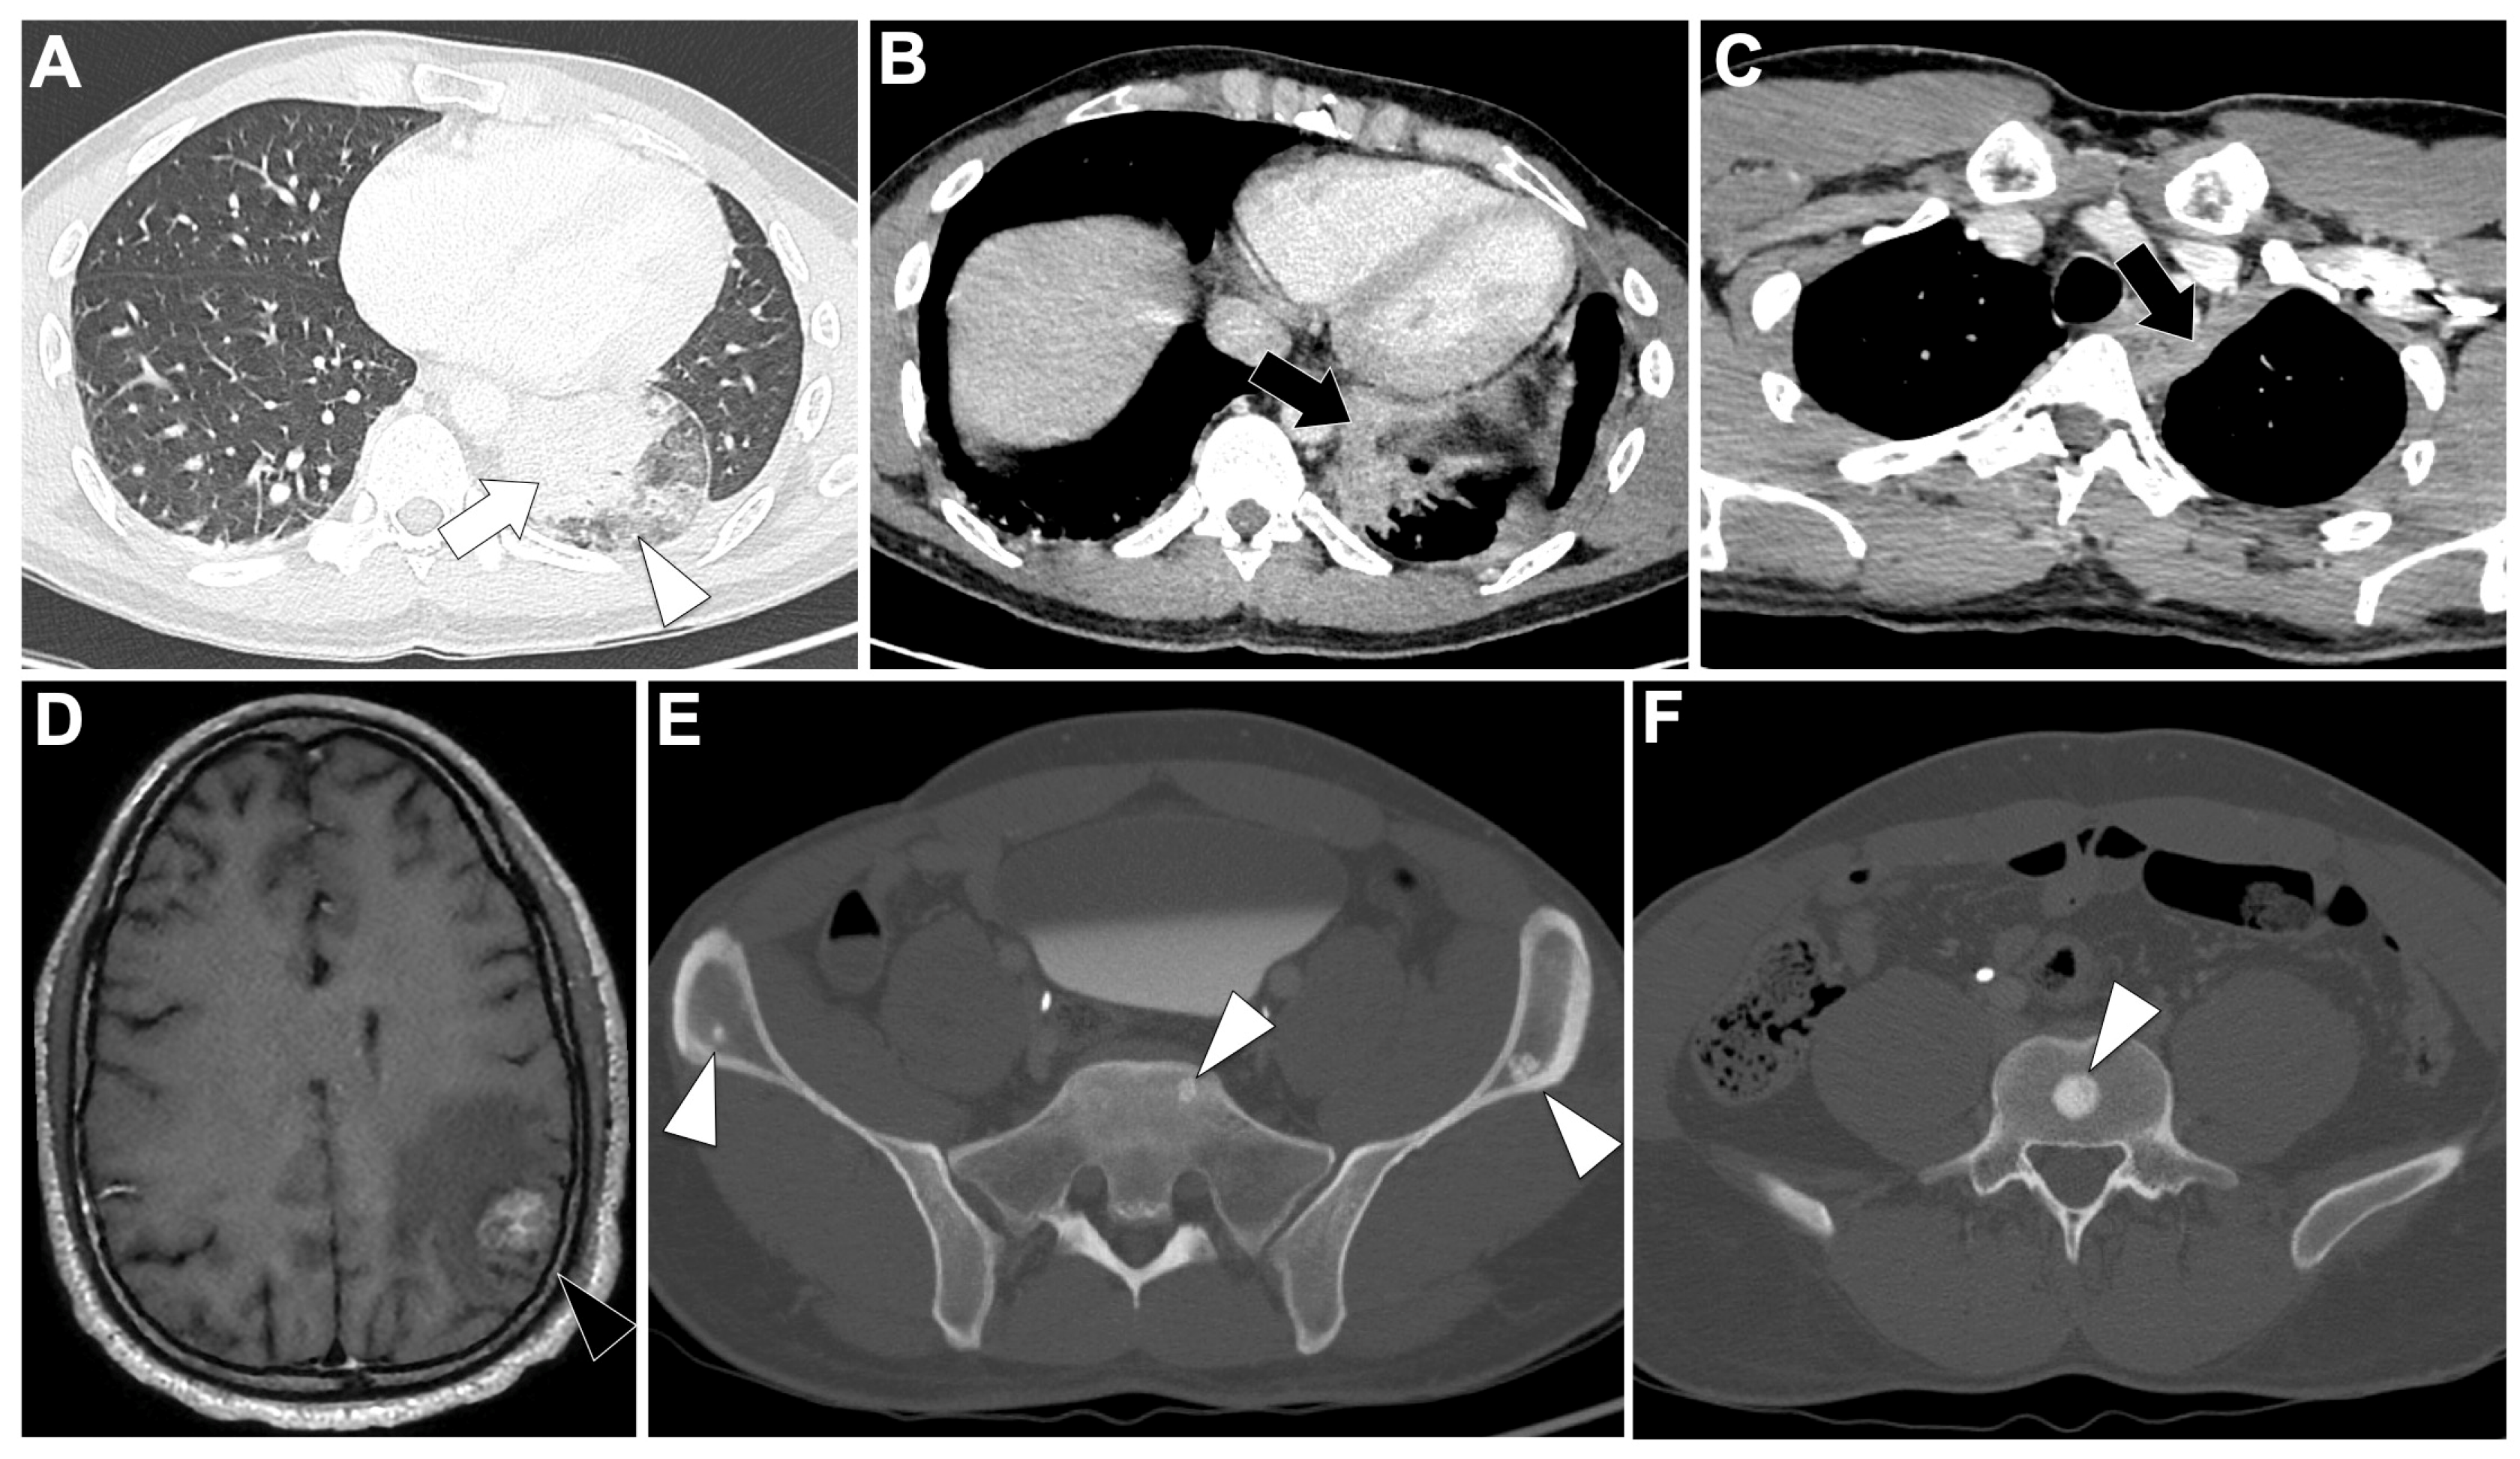

3.6. MET Exon 14-Altered NSCLC (Figure 6)

3.6.2. Radiological Characteristics of the Primary Lung Lesion in MET Exon 14-Altered LUAD

3.6.3. Metastatic Pattern in MET Exon 14-Altered LUAD